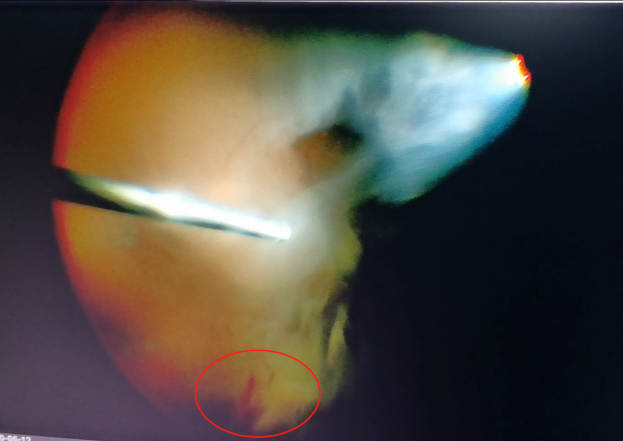

(左為玻璃體切割術(shù)中,明顯可見有積血;右為激光治療后的眼底)

手術(shù)中,醫(yī)生們先后為程先生行白內(nèi)障超聲乳化術(shù)及后入路玻璃體切割術(shù),并置入人工晶體。手術(shù)僅用半個(gè)小時(shí)便順利完成。